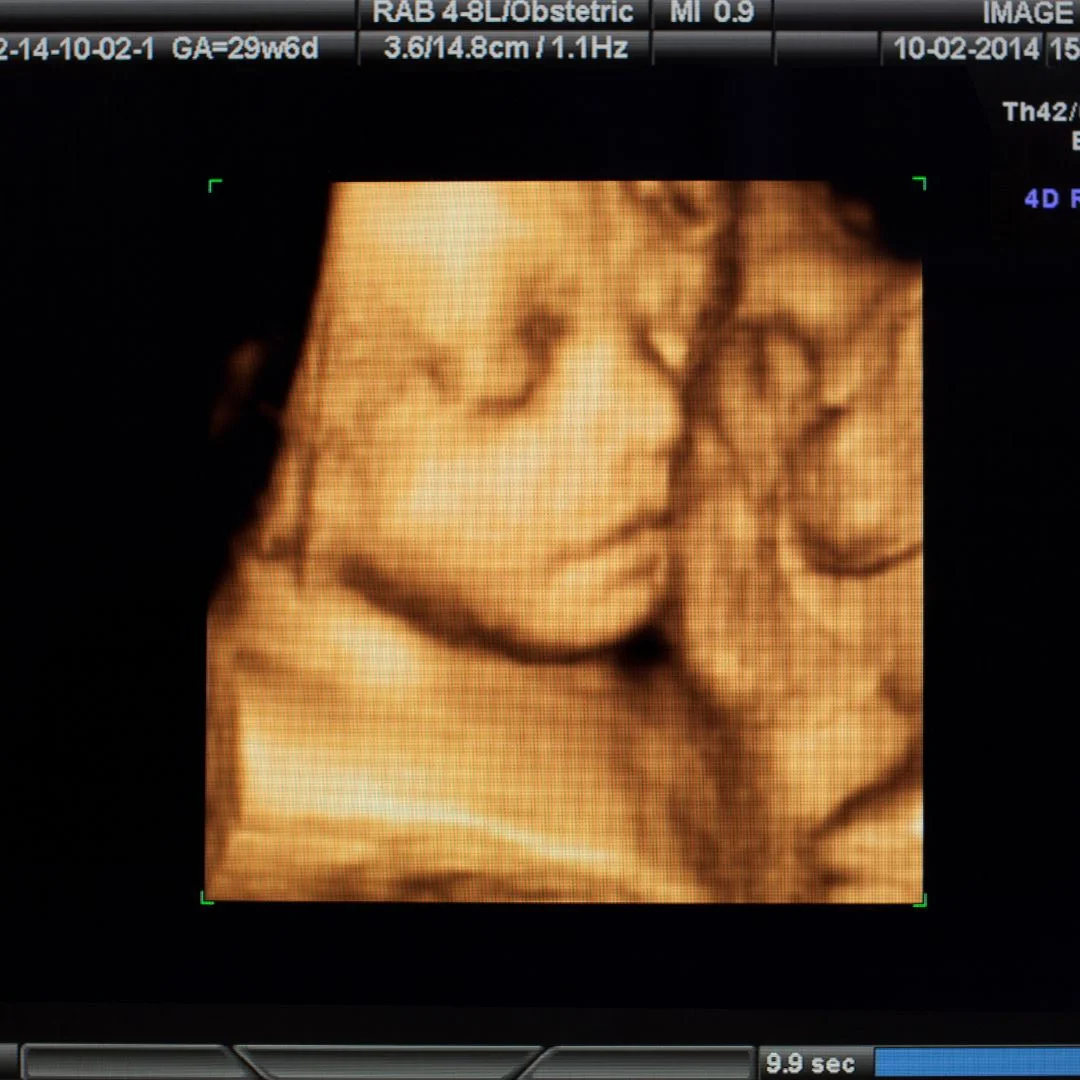

Regular ultrasounds use two-dimensional and black-and-white images, while 3D ultrasounds provide parents with a three-dimensional image of their baby that can be viewed in color. This improved image quality allows for greater detail and produces a more realistic view of the baby’s features so you can get a more accurate idea of how your little one looks. A traditional ultrasound generally takes a few minutes to get the required images, while a 3D ultrasound interaction can last up to 15 minutes or longer depending on how cooperative your baby is. This extended time helps capture better visual information and allows you to take pictures with the 3D ultrasound machine. A 3D ultrasound produces images that show the baby’s facial features and body movements. This allows you to get a better look at your unborn baby, allowing you to monitor their growth and development during pregnancy. It also gives you an opportunity to see the details of your little one’s face, jaw, lips, nose, and eyes in more detail than a regular ultrasound. Regular ultrasounds are available in most medical facilities, but 3D ultrasounds for pregnancy may not be as easy to access. Sweet Baby Face is here to provide families with the highest quality service when it comes to 3D ultrasound technology. Our team is specifically trained to help expecting mothers get a better view of their little one.

Level of Detail in Images